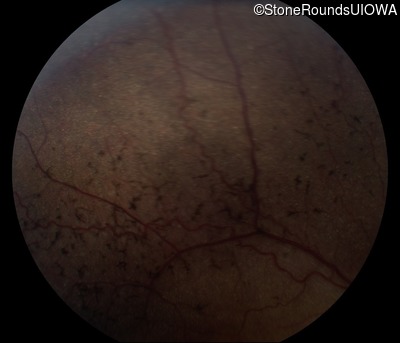

Fundus Photography - Left - 20/80 -1

Exemplar